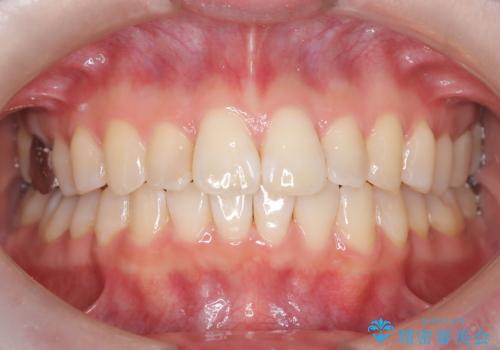

[ マウスピース矯正 ] がたがたした歯並びを治したい

担当医 大元洋佑

![[ マウスピース矯正 ] がたがたした歯並びを治したいの症例 治療前](https://seimitsushinbi.jp/wp/wp-content/uploads/2024/04/IMG_0106-500x350.jpg?v=1711951424)

![[ マウスピース矯正 ] がたがたした歯並びを治したいの症例 治療後](https://seimitsushinbi.jp/wp/wp-content/uploads/2024/04/46939b7482334672d3a091da1562afec-500x350.jpg?v=1711951403)